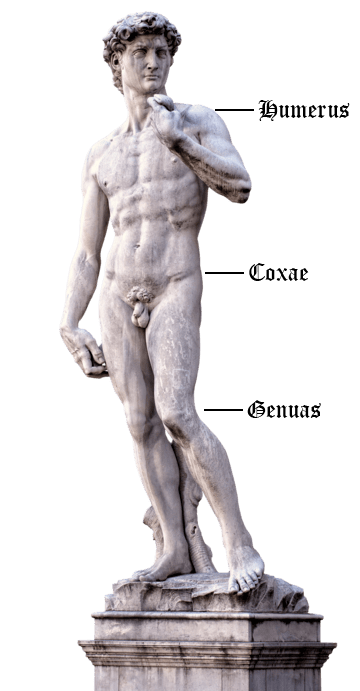

Michelangelo perfected the human form. We perfect the components that keep it moving.

At HK Orthopedics, we understand every BODY is built differently. That’s why our shoulder, hip, and knee components are crafted with precision engineering to match each patient’s unique anatomy and deliver long-lasting, dependable support.

Click on the statue of David's shoulder, hips, and knees to learn more about our products!

Shoulder

HK Orthopedics manufactures durable components for shoulder replacement surgery, designed to restore joint motion, reduce pain, and provide long-lasting strength and stability.

Shoulder

HK Orthopedics manufactures durable components for shoulder replacement surgery, designed to restore joint motion, reduce pain, and provide long-lasting strength and stability.

Hips

We produce precision hip replacement components that restore smooth joint movement, reduce pain, and provide strong, long-lasting stability for patients.

Hips

We produce precision hip replacement components that restore smooth joint movement, reduce pain, and provide strong, long-lasting stability for patients.

Knees

HK Orthopedics produces high-precision components used in knee replacement surgery that restore smooth movement, reduce pain, and provide long-lasting stability for patients.

HK Orthopedics designs and manufactures high-quality components used in shoulder replacement surgery. Our glenoid and humeral implants are engineered to replicate the natural shape and motion of the shoulder joint, helping restore smooth mobility and reduce chronic pain caused by arthritis or injury. Made from durable, biocompatible materials, each component is built for long-term stability, strength, and reliable performance. Surgeons trust HK Orthopedics for precision-crafted parts that support faster recovery and help patients return to comfortable, confident movement.

HK Orthopedics designs and manufactures precision-engineered hip replacement components that help patients regain mobility and improve quality of life. Each implant is crafted to restore smooth, natural joint movement while minimizing discomfort and reducing pain. With a focus on durability and long-term stability, HK Orthopedics’ hip components are built to withstand the demands of daily activity, giving patients confidence and freedom in their movements. Backed by advanced engineering and rigorous quality standards, our implants provide reliable performance, allowing individuals to return to an active, pain-free lifestyle.

HK Orthopedics manufactures precision-engineered components used in knee replacement surgery. Our femoral, tibial, and patellar implant parts are designed to restore smooth joint movement, reduce pain, and provide long-lasting stability. Each component is made from durable, biocompatible materials that replicate the function of natural bone and cartilage, helping patients regain strength, mobility, and confidence after surgery.